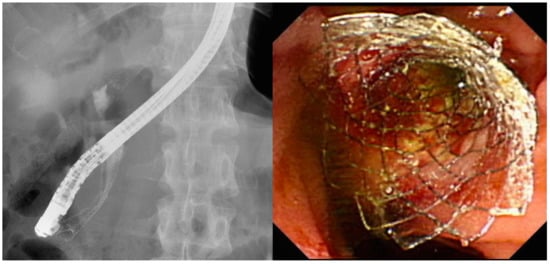

- Chahal, P.; Baron, T.H. Expandable metal stents for endoscopic bilateral stent-within-stent placement for malignant hilar biliary obstruction. Gastrointest. Endosc. 2010, 71, 195–199. [Google Scholar] [CrossRef] [PubMed]

- Kogure, H.; Isayama, H.; Kawakubo, K.; Sasaki, T.; Yamamoto, N.; Hirano, K.; Sasahira, N.; Tsujino, T.; Tada, M.; Koike, K. Endoscopic bilateral metallic stenting for malignant hilar obstruction using newly designed stents. J. Hepatobiliary Pancreat. Sci. 2011, 18, 653–657. [Google Scholar] [CrossRef]

- Hwang, J.C.; Kim, J.H.; Lim, S.G.; Kim, S.S.; Yoo, B.M.; Cho, S.W. Y-shaped endoscopic bilateral metal stent placement for malignant hilar biliary obstruction: Prospective long-term study. Scand. J. Gastroenterol. 2011, 46, 326–332. [Google Scholar] [CrossRef]

- Kogure, H.; Isayama, H.; Nakai, Y.; Tsujino, T.; Ito, Y.; Yamamoto, K.; Mizuno, S.; Yagioka, H.; Kawakubo, K.; Sasaki, T.; et al. Newly designed large cell Niti-S stent for malignant hilar biliary obstruction: A pilot study. Surg. Endosc. 2011, 25, 463–467. [Google Scholar] [CrossRef]

- Saleem, A.; Baron, T.H.; Gostout, C.J. Large-diameter therapeutic channel duodenoscope to facilitate simultaneous deployment of side-by-side self-expandable metal stents in hilar cholangiocarcinoma. Gastrointest. Endosc. 2010, 72, 628–631. [Google Scholar] [CrossRef]

- Park, D.H.; Lee, S.S.; Moon, J.H.; Choi, H.J.; Cha, S.W.; Kim, J.H.; Seo, D.W.; Lee, S.K.; Park, S.H.; Lee, M.S.; et al. Newly designed stent for endoscopic bilateral stent-in-stent placement of metallic stents in patients with malignant hilar biliary strictures: Multicenter prospective feasibility study (with videos). Gastrointest. Endosc. 2009, 69, 1357–1360. [Google Scholar] [CrossRef]